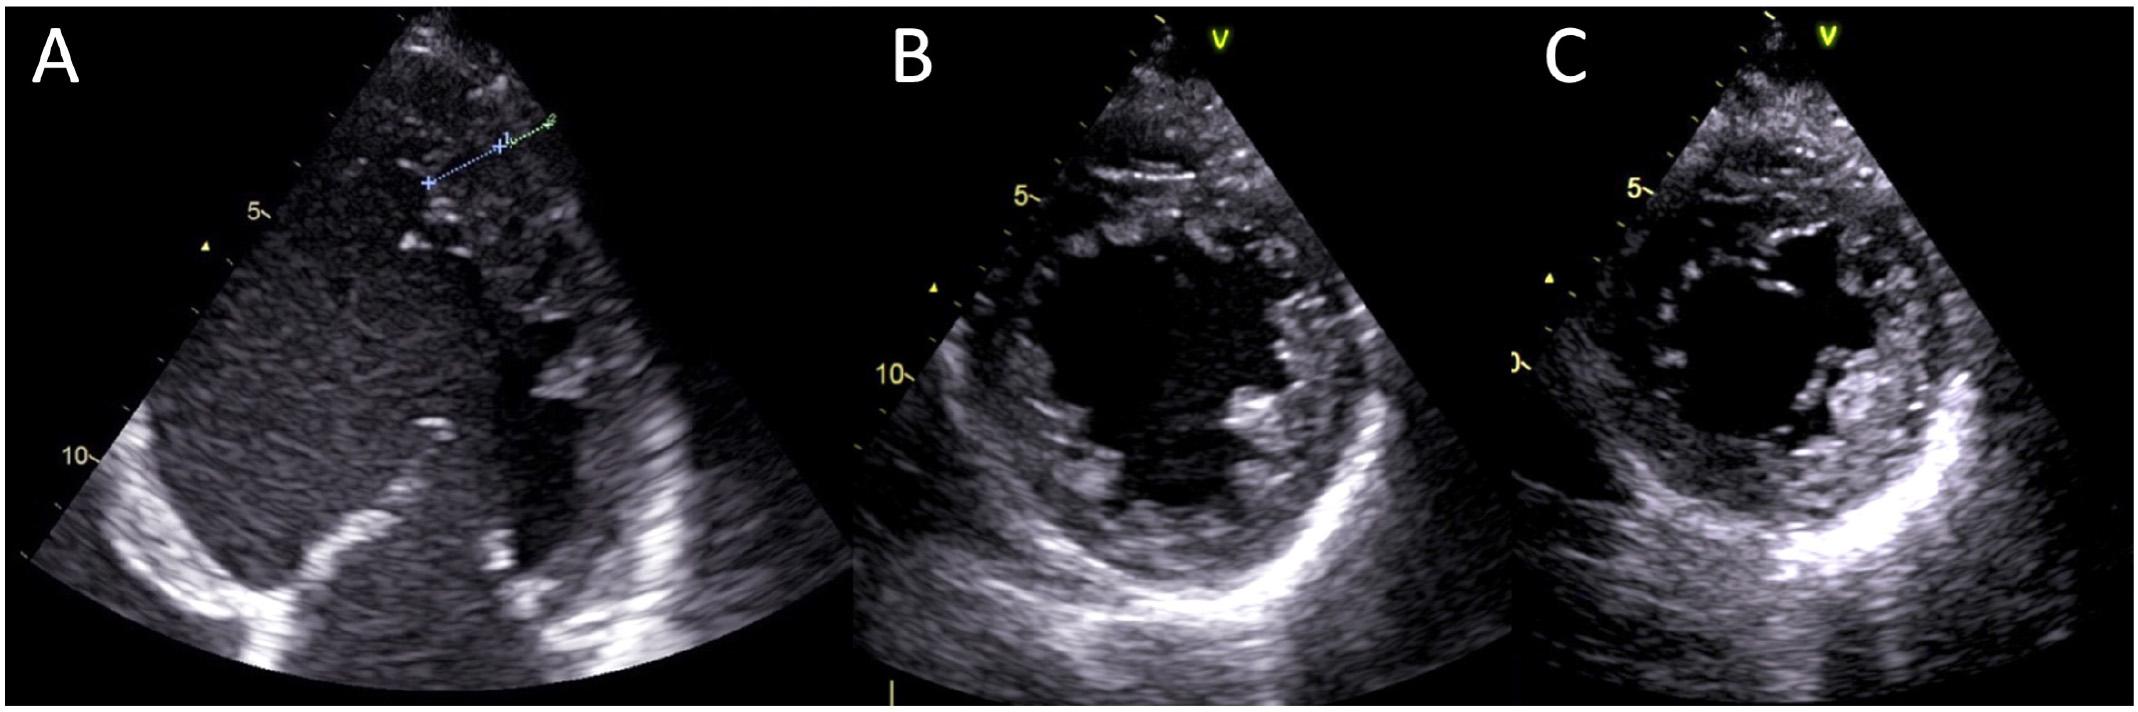

Figure 3